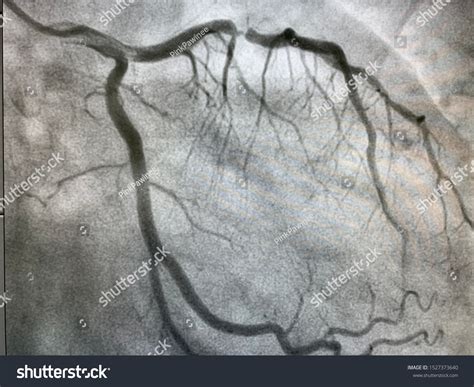

Because the Left Main Artery is so vital, cardiologists use highly precise diagnostic tools to evaluate the extent of any blockage. These tests allow doctors to map out the severity of the stenosis and decide on the most appropriate surgical or non-surgical intervention.

Coronary Angiogram The "gold standard" for imaging the lumen of the artery. Very High